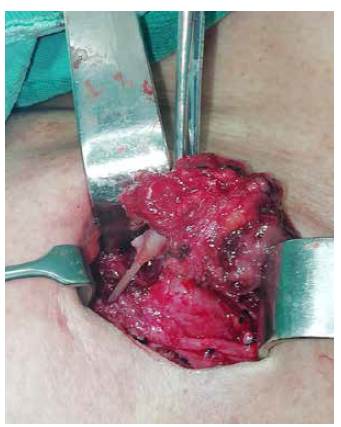

Dado el tiempo de evolución y el compromiso extraluminal del cuerpo extraño, se procedió a la exploración quirúrgica y se encontró tejido fibrótico en la región posterior del lóbulo tiroideo izquierdo, como reacción a un cuerpo extraño espinoso que perforó la pared antero-lateral del esófago cervical y comprometía la adventicia, por lo cual se practicó una tiroidectomía subtotal izquierda.

La técnica abierta suele ser la principal elección, pues permite llegar fácilmente al sitio lesionado, así como evitar lesiones de otras estructuras adyacentes por la visualización directa 12,5,8,10. Entre otras, estas fueron las razones por las que se decidió la cirugía abierta en esta paciente (figura 4).